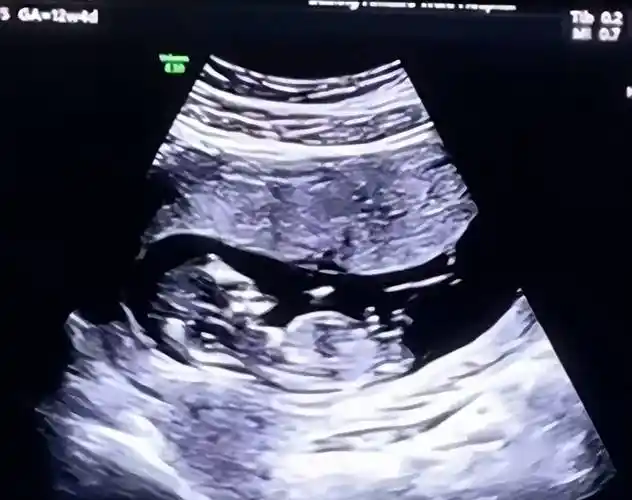

陈龙章龄之闪婚闪孕 双喜临门甜蜜晒婴儿b超照